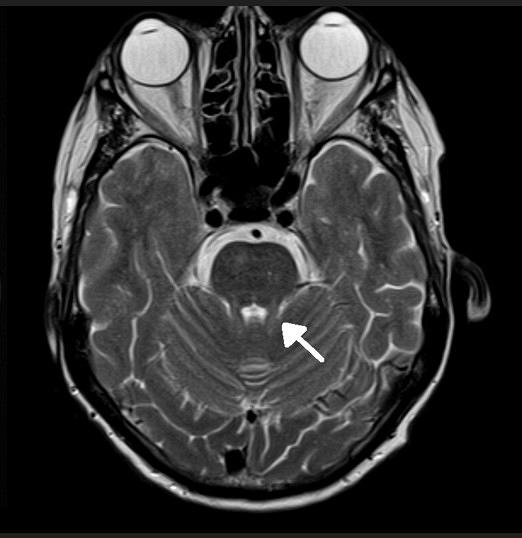

• kent u de specifieke klinische en radiologische kenmerken die op SCA27b en RFC1 kunnen wijzen